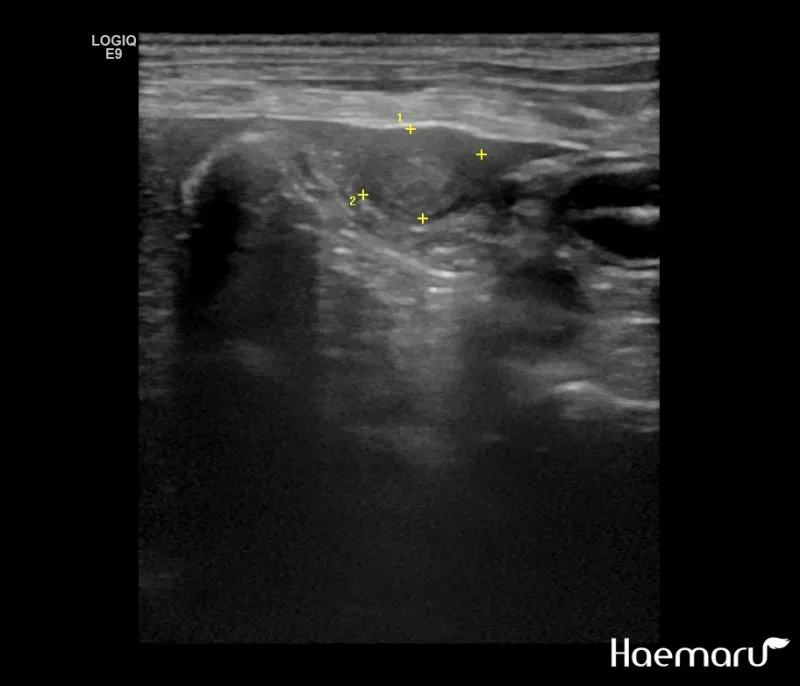

복부 초음파 검사 - 가장 기본적이면서도 중요한 1차 검사예요. 췌장의 크기나 모양 변화, 주변 장기와의 관계를 실시간으로 관찰할 수 있어요. 비용은 보통 15만원-25만원 정도이고, 검사 시간은 20-30분 정도 걸립니다.

CT와 MRI 검사 - 초음파에서 의심스러운 소견이 발견되면 더 정밀한 검사를 진행해요. 특히 3D 영상으로 종양의 정확한 위치와 크기를 파악할 수 있어서 수술 계획을 세우는 데 필수적이에요.